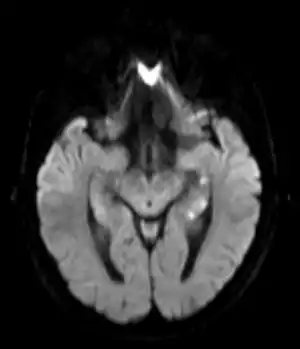

| Transiente globale Amnesie MRT DWI axial | |